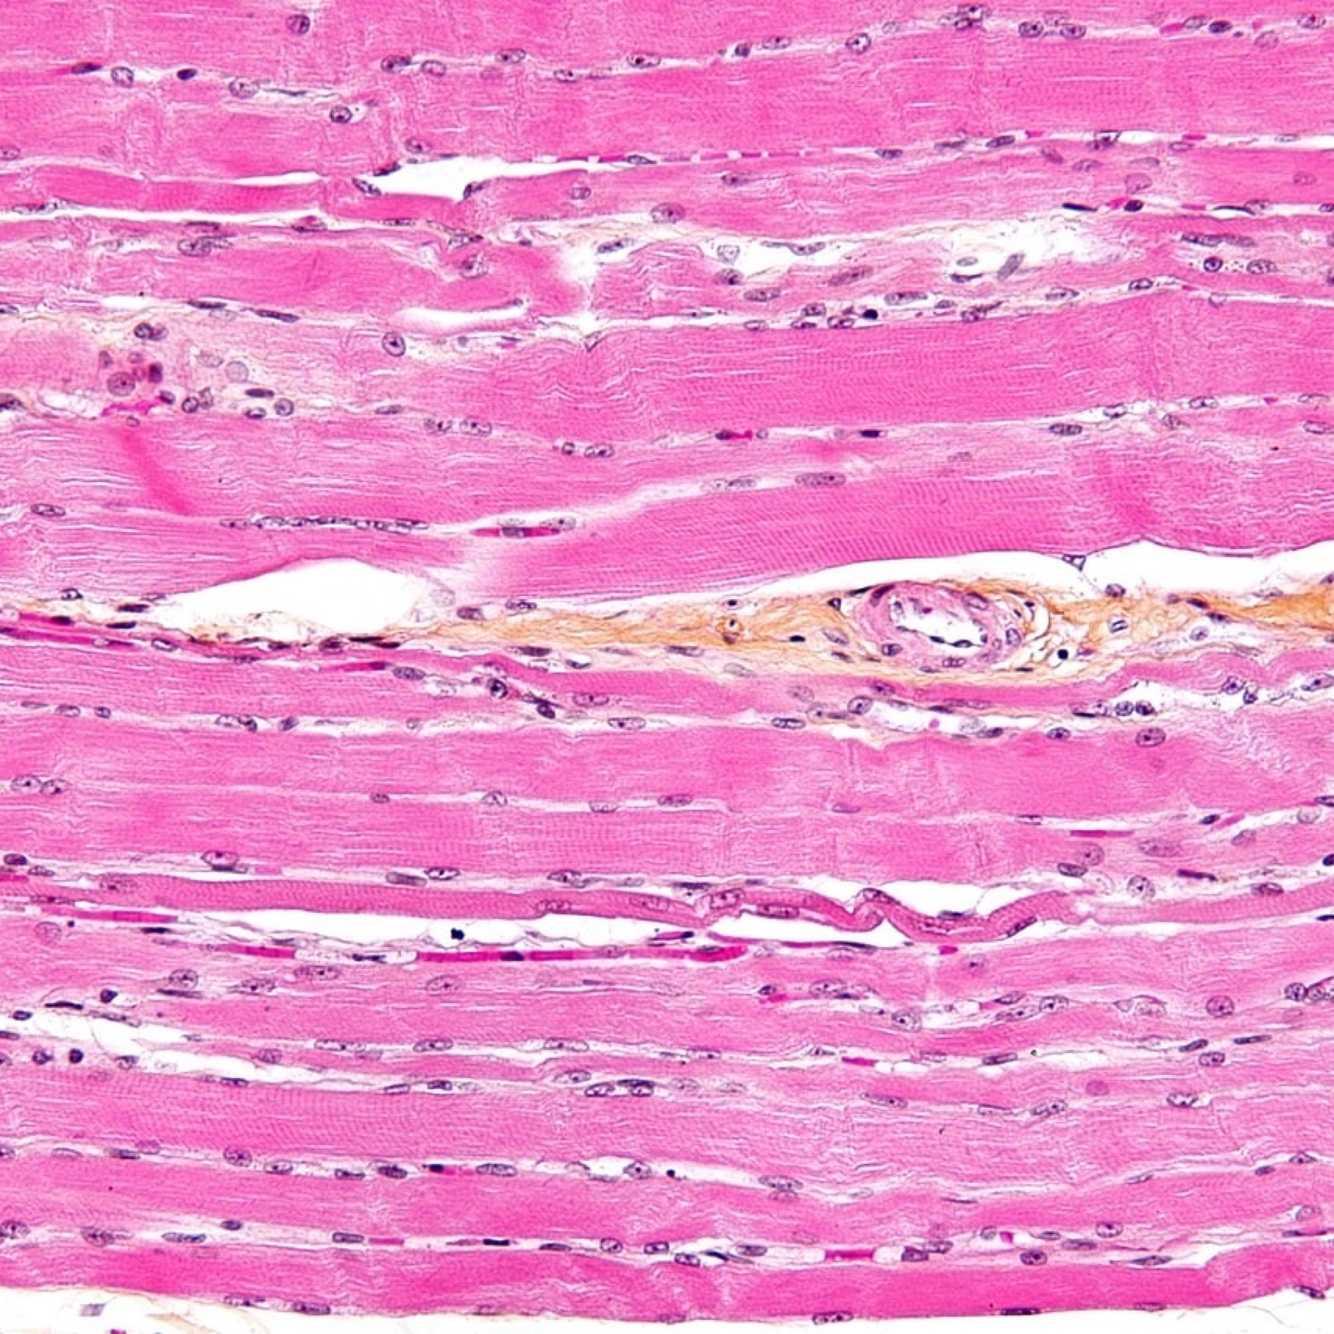

8

Q

ID the muscle tissue

A

Cardiac Muscle tissue